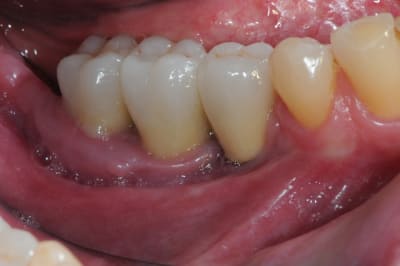

3 aspect (in vivo)

:)